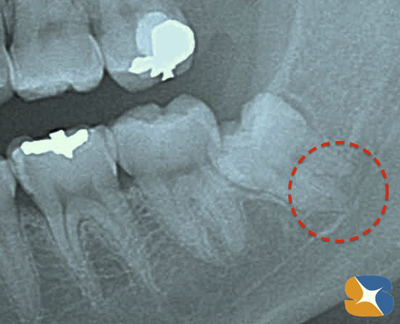

レントゲン撮影の結果、歯が下顎の骨の深い位置に埋まっていました。

さらに詳しく調べるため、CT撮影を院内で実地。すると、アゴ骨を走行する太い神経と歯の根の先が交差していることも判明。